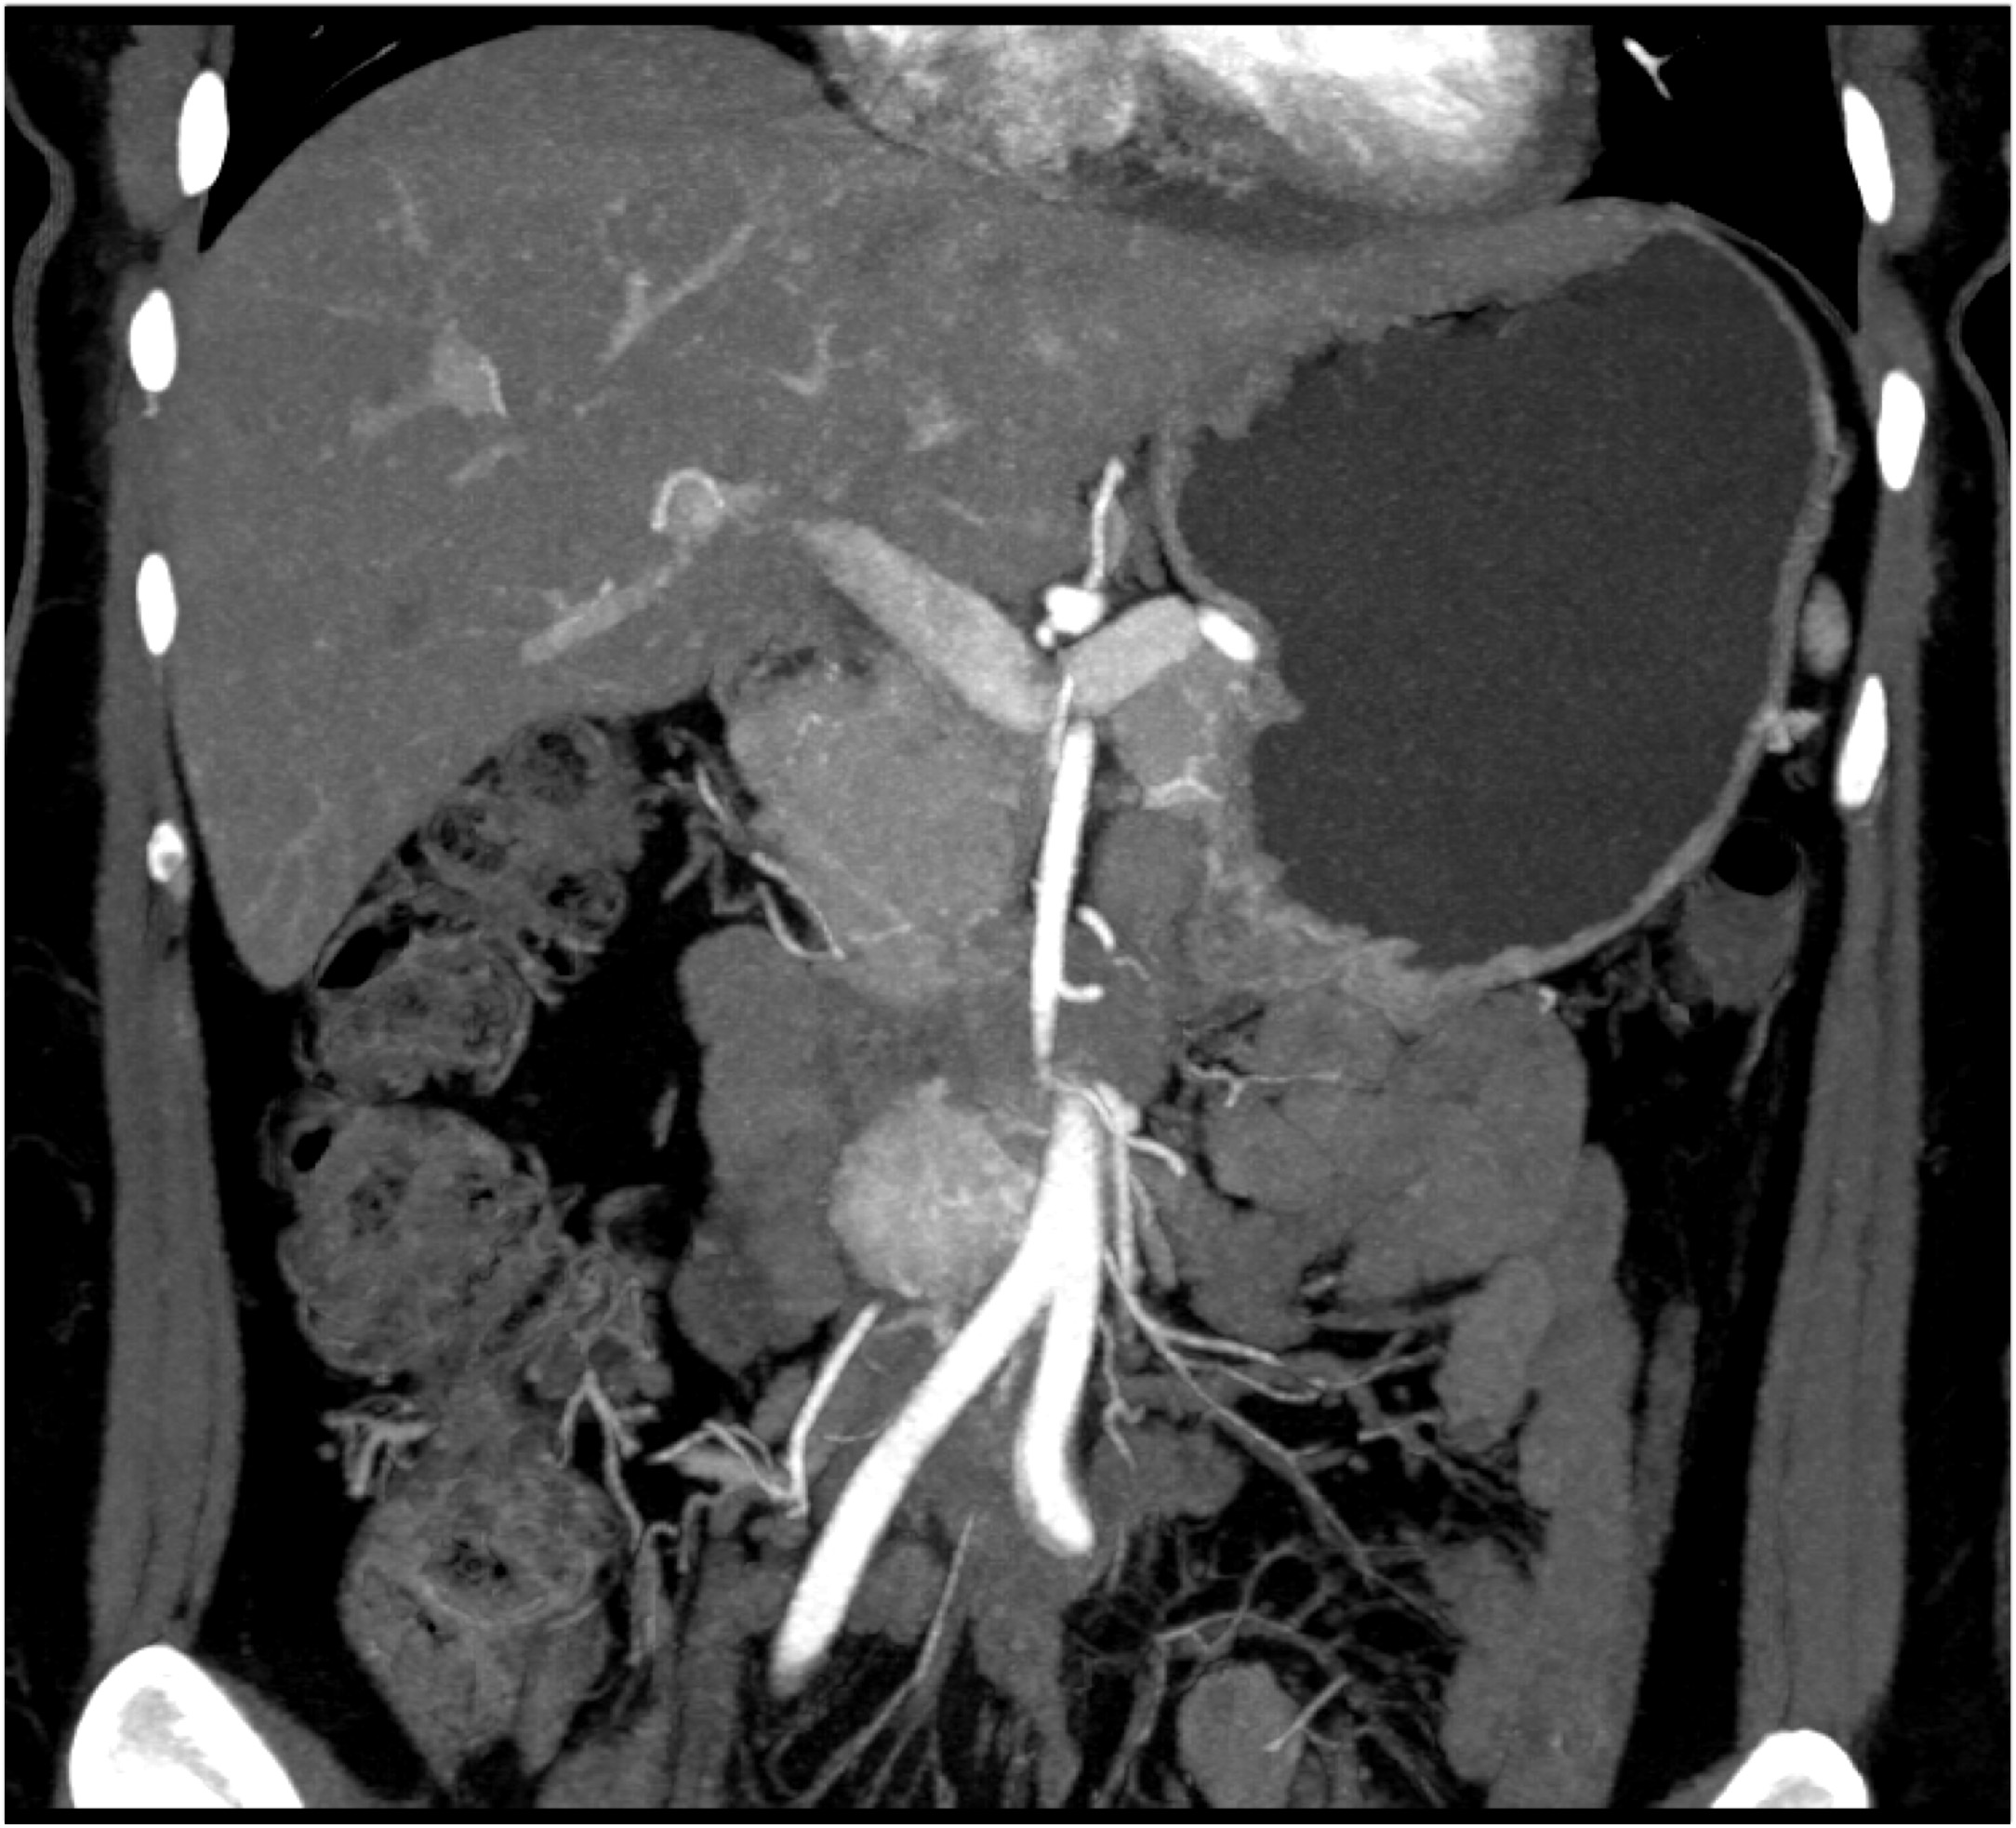

2) The least likely diagnosis in this case is?

hepatoma

cholangiocarcinoma

metastatic disease to the liver

hemangioma